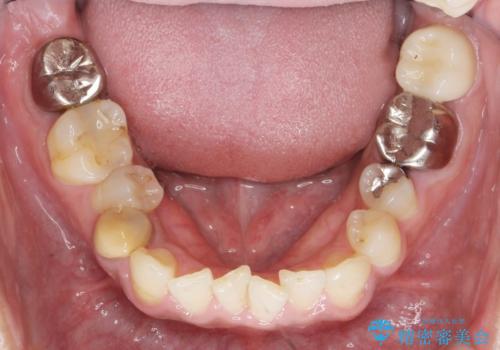

- 治療計画

- 長年虫歯の治療を受け続けたことで銀歯・コンポジットレジン修復だらけになってしまい、今後の見た目や歯を大切にするためにセラミック治療矯正治療を希望され来院されました。

マイクロスコープを用いた精密根管治療やセラミック治療、マウスピース矯正治療を一つの医院で行うことのできる当法人ならではの総合歯科治療を実践していきます。